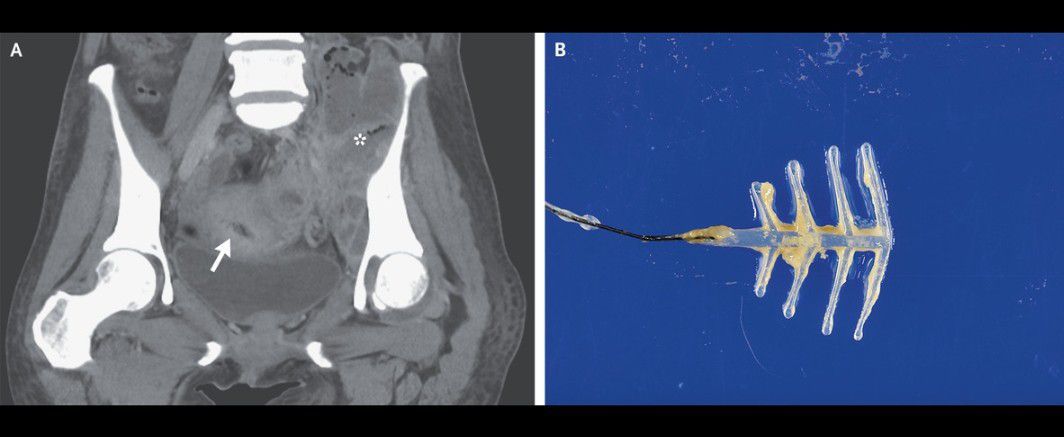

A 54-year-old woman presented to the emergency department with a 2-month history of fevers and weight loss and a 3-week history of abdominal pain and difficulty walking. Her temperature was 38.5°C. Examination was notable for a tender mass in the left lower quadrant of the abdomen. Laboratory studies showed a white-cell count of 30,420 per cubic millimeter (reference range, 3300 to 8600). Contrast-enhanced computed tomography (CT) revealed an intrauterine device (IUD) (Panel A, arrow) surrounded by multiple abscesses (asterisk) throughout the abdomen and pelvis that extended into the left iliopsoas muscle and left hip joint. The patient underwent CT-guided drainage of the abscesses, washout of the left hip joint, and removal of the IUD, which was coated in sulfur-colored granules (Panel B). Gram’s staining of fluid samples revealed branching, filamentous, gram-positive rods. Actinomyces israelii was grown on culture. The patient reported that the IUD had been inserted more than two decades before presentation and had not been replaced since that time. After a prolonged course of intravenous antibiotics followed by oral antibiotics, the patient’s abdominal and hip pain abated.